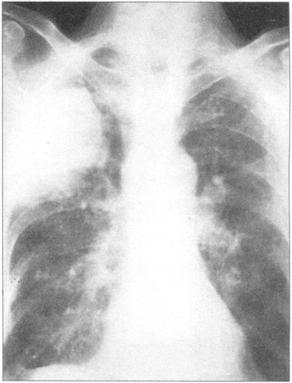

①周围性发绀及周围静脉扩张是由COPD引起的CO2潴留的主要特征(图76)。②脊柱侧后凸常预示患者有某种呼吸系统疾病的倾向(图77)。③结核的X线表现(图78)。④肺尖部结核所致的纤维化多引起上胸部变平(图79),由于脊柱常受累,故多有成角。⑤支气管肺癌(图80)。⑥大叶肺炎患者常伴发单纯疱疹病毒感染(图81、图82)。⑦如肺组织萎陷(如气胸),则胸片上无法看到肺纹理(图83)。

图81 大叶性肺炎,这个患者有右肺实变

图82 单纯疱疹病毒感染在大叶性肺炎患者常见